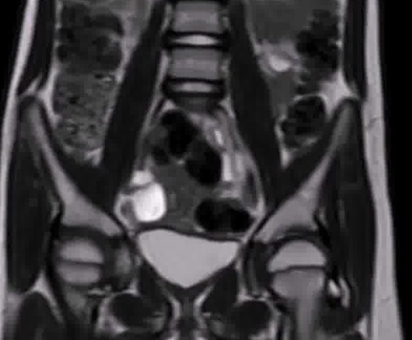

Initial Experiences of Treating Prostate Cancer with Focal Irreversible Electroporation

Authors: John Torosyan, Shima Tayebi, Wei-Wen Hsu, and Abhinav Sidana

View Video